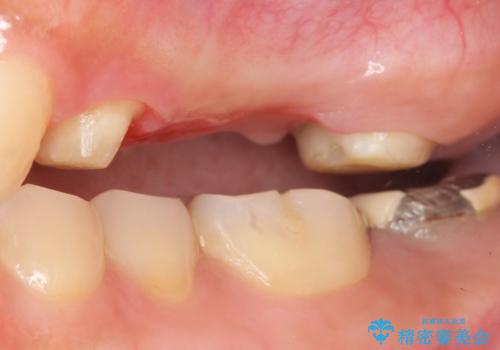

- う蝕により奥歯がボロボロになってしまい、咬むことができないことを主訴に来院された患者様です。

奥歯3本(左上567)はう蝕が深く保存不可能な状態であったため、やむなく抜歯しました。

インプラントも入れ歯も抵抗があるとのご相談により、自家歯牙移植を提案しました。

使っていない親知らず(左上8)を左上7抜歯窩に移植し、支台歯としてブリッジによる補綴治療を行いました。